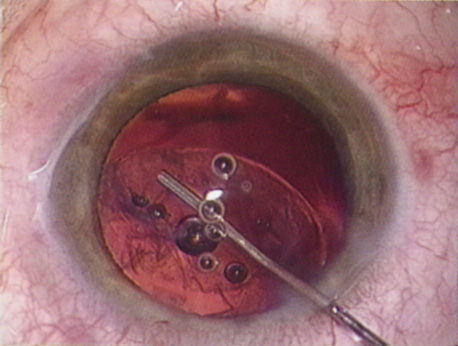

The introduction of innovative adjunctive devices was able to improve the management of challenging cases. The capsular tension ring introduced independently by Tsutomu Hara37 and Toshiyuki Nagamoto38 in Japan was identified as a major weapon in managing zonular weakness by Ulrich Legler and Bernd Witschel of Germany.39 The CTR came to the United States in 1993,40 after which modifications by Robert Cionni,41 Iqbalk Ahmed and Alan Crandall,42 and Burkhard Dick were developed. Iris reconstruction had been primarily limited to suture techniques developed by Malcolm McCannel43 and later Steven Siepser.44 The prosthetic irides were introduced by German surgeons, Ranier Sundmacher45 and Volker Rasch,46 and brought to the United States by Kenneth Rosenthal and then Robert Osher in 1996.47 Although many devices had been developed to mechanically open the small pupil, it was the stretch technique developed by Luther Fry that greatly simplified these difficult cases.48 Improving visibility by staining the anterior capsule of the white cataract was introduced by Masayuki Horiguchi from Japan (ICG)49 and Gerritt RJ Melles from The Netherlands (Trypan Blue).50